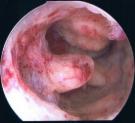

Schließlich ist die Ultraschalluntersuchung auch in der Lage, zur frühzeitigen Entdeckung von Krebserkrankungen beizutragen, wie auf dem unteren Beispiel: links wieder das Ultraschallbild (diesmal zwei Aufnahmen in unterschiedlichen Ebenen, die hellen Strukturen sind die verdächtigen Gewebsanteile), rechts die Veränderungen bei der anschließenden Gebärmutterspiegelung: polypöse Strukturen mit Übergang in einen Gebärmutterkörperkrebs.